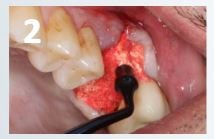

• The OsteoGen® Plug is condensed firmly into the socket. Enough material should be used and positioned above the crest (to the level of or slightly below the soft tissue). (Fig. 2)